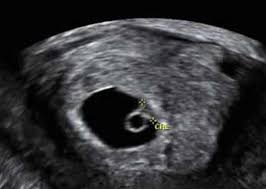

Your baby s heartbeat should be between 90 110 beats per minute bpm at 6 to 7 weeks. Finding a fetal heartbeat on a handheld doppler can take even longer. If you are at least eight or nine weeks along at your first prenatal visit your doctor or midwife may use a fetal doppler or a fetal doppler stethoscope to pick up the sound of your baby s heart beating. Once at 9 weeks.

Discussion in pregnancy first trimester started by amz0109 feb 7 2012. It will be about 170 beats per minutes by this time a rate that will slow from here on out.Source : pinterest.com